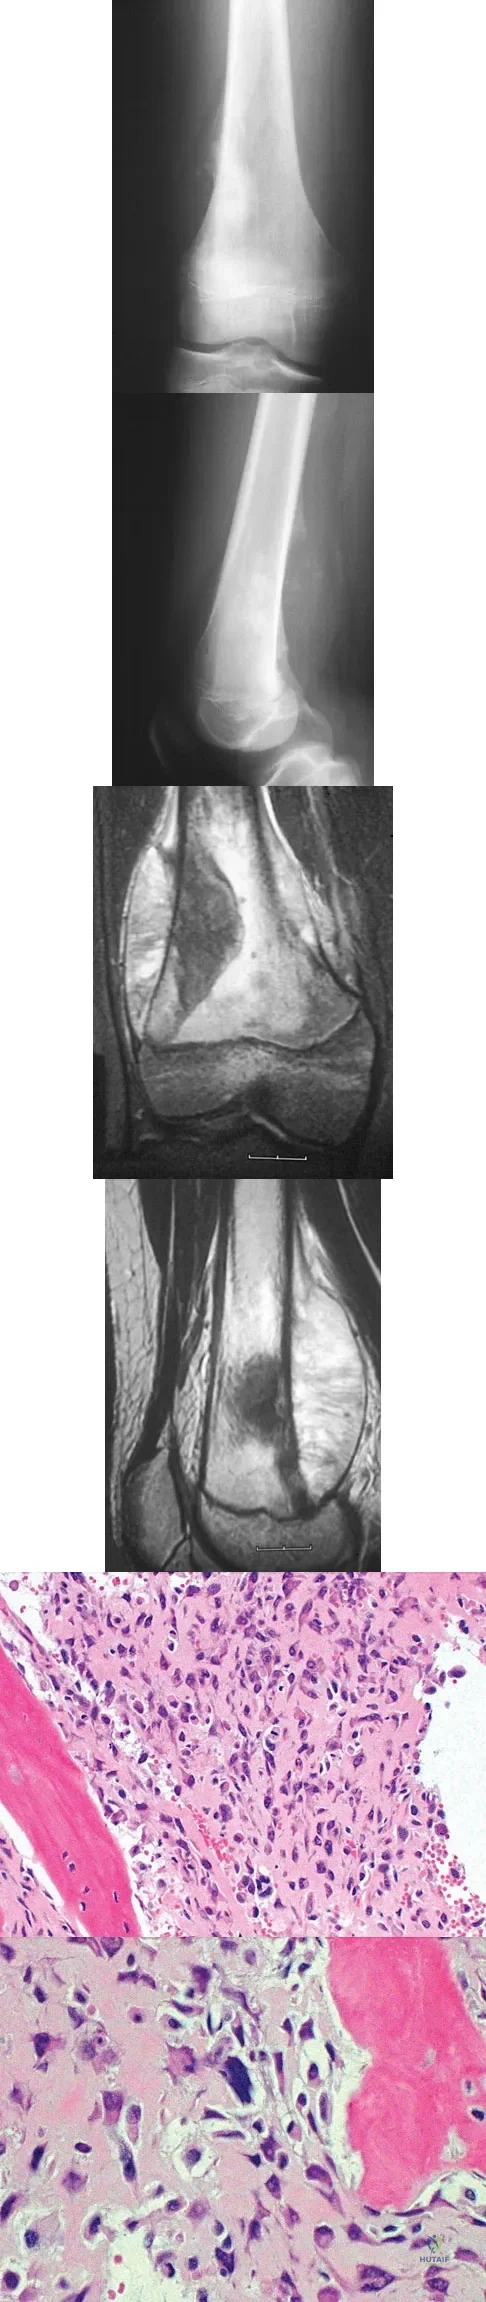

Question 45High Yield

A 13-year-old boy has knee pain after sustaining a mild twisting injury while playing basketball 4 weeks ago. Radiographs and MRI scans are shown in Figures 24a through 24d, and biopsy specimens are shown in Figures 24e and 24f. Treatment should consist of

Explanation